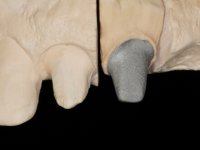

Endodontic treatments were performed and a metalic non screwed intra radicular post was placed on tooth 1.1. An alginate impression was made for laboratory confection of a reinforced acrylic provisional bridge, with teeth 1.1 and 2.2 as abutments and 2.2 as a pontic. After preparation of tooth 1.1 and root preparation of 2.1, the bridge was relined in mouth with self-polymerizable acrylic using a metal post for further retaining the prepared root canal on 2.1. Tooth 2.2 was cut at the gingival level to function as support. In the same session, the impression of the root canal of the 2.1 was made for the laboratory confection of a cast post and core. A double mixture technique with plastic tutor was used after previous canal vaseline with endodontic file and cotton. The provisional bridge was provisionally cemented and the cast post and core was made in the laboratory. Cast post and core cementation was made with resin-reinforced glass ionomer cement and the provisional bridge had to be readjusted to the new situation by removing the post at the site of 2.1. After careful surgical planning, a dental implant was placed, simultaneously with extraction of the root of tooth 2.2. The provisional bridge was placed by resting on the healing screw placed in the implant. The respected osteointegration period was 12 weeks, during which the provisional bridge was relined twice. After complete maturation of hard and soft tissues, definitive impressions were made. The gingival retraction technique was applied with an impregnated retraction cord and impression was performed using double mixture, open tray impression technique. A custom precious metal abutment implant was prepared in the lab, along with 3 metal caps to be used as infrastructures for the metal ceramic crowns. Particular care was taken in the confection of the cervical finishing line of the implant abutment, in order to follow the soft tissues emergence profile. Proof of infrastructures was done in the mouth being evaluated clinically and imagiologically. Collection of color information was done by the ceramist at the office. Ceramic was applied in the laboratory and the finished work was placed in the mouth after approval by the patient. Definitive cementation was made with resin-reinforced glass ionomer cement, and the first crown to be cemented was that of the implant, to facilitate removal of the excess.